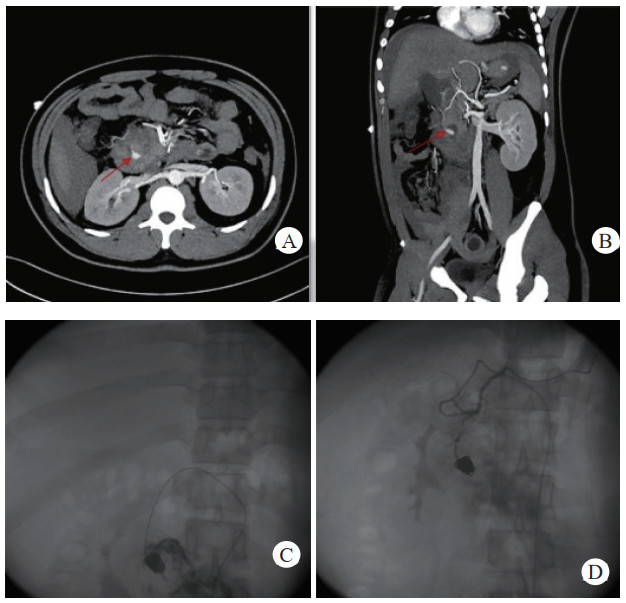

介入栓塞成功率为100%,术中栓塞后即刻复查造影显示,载瘤动脉或假性动脉瘤瘤腔不复显影及未见对比剂外溢,栓塞成功,见图 1(病例1)。

| 注:A、B为患者术前CT增强扫描,示胰腺炎影像,胰头下方血肿影像,中央可见与血管强化方式相同的动脉瘤影像(箭头示),其供血动脉为胰十二指肠上动脉;C为DSA示对比剂充满瘤腔并见对比剂外溢;D为DSA示介入栓塞术后,弹簧圈填满瘤腔及未见对比剂外溢 图 1 病例1术前、术后CT平扫及增强 |